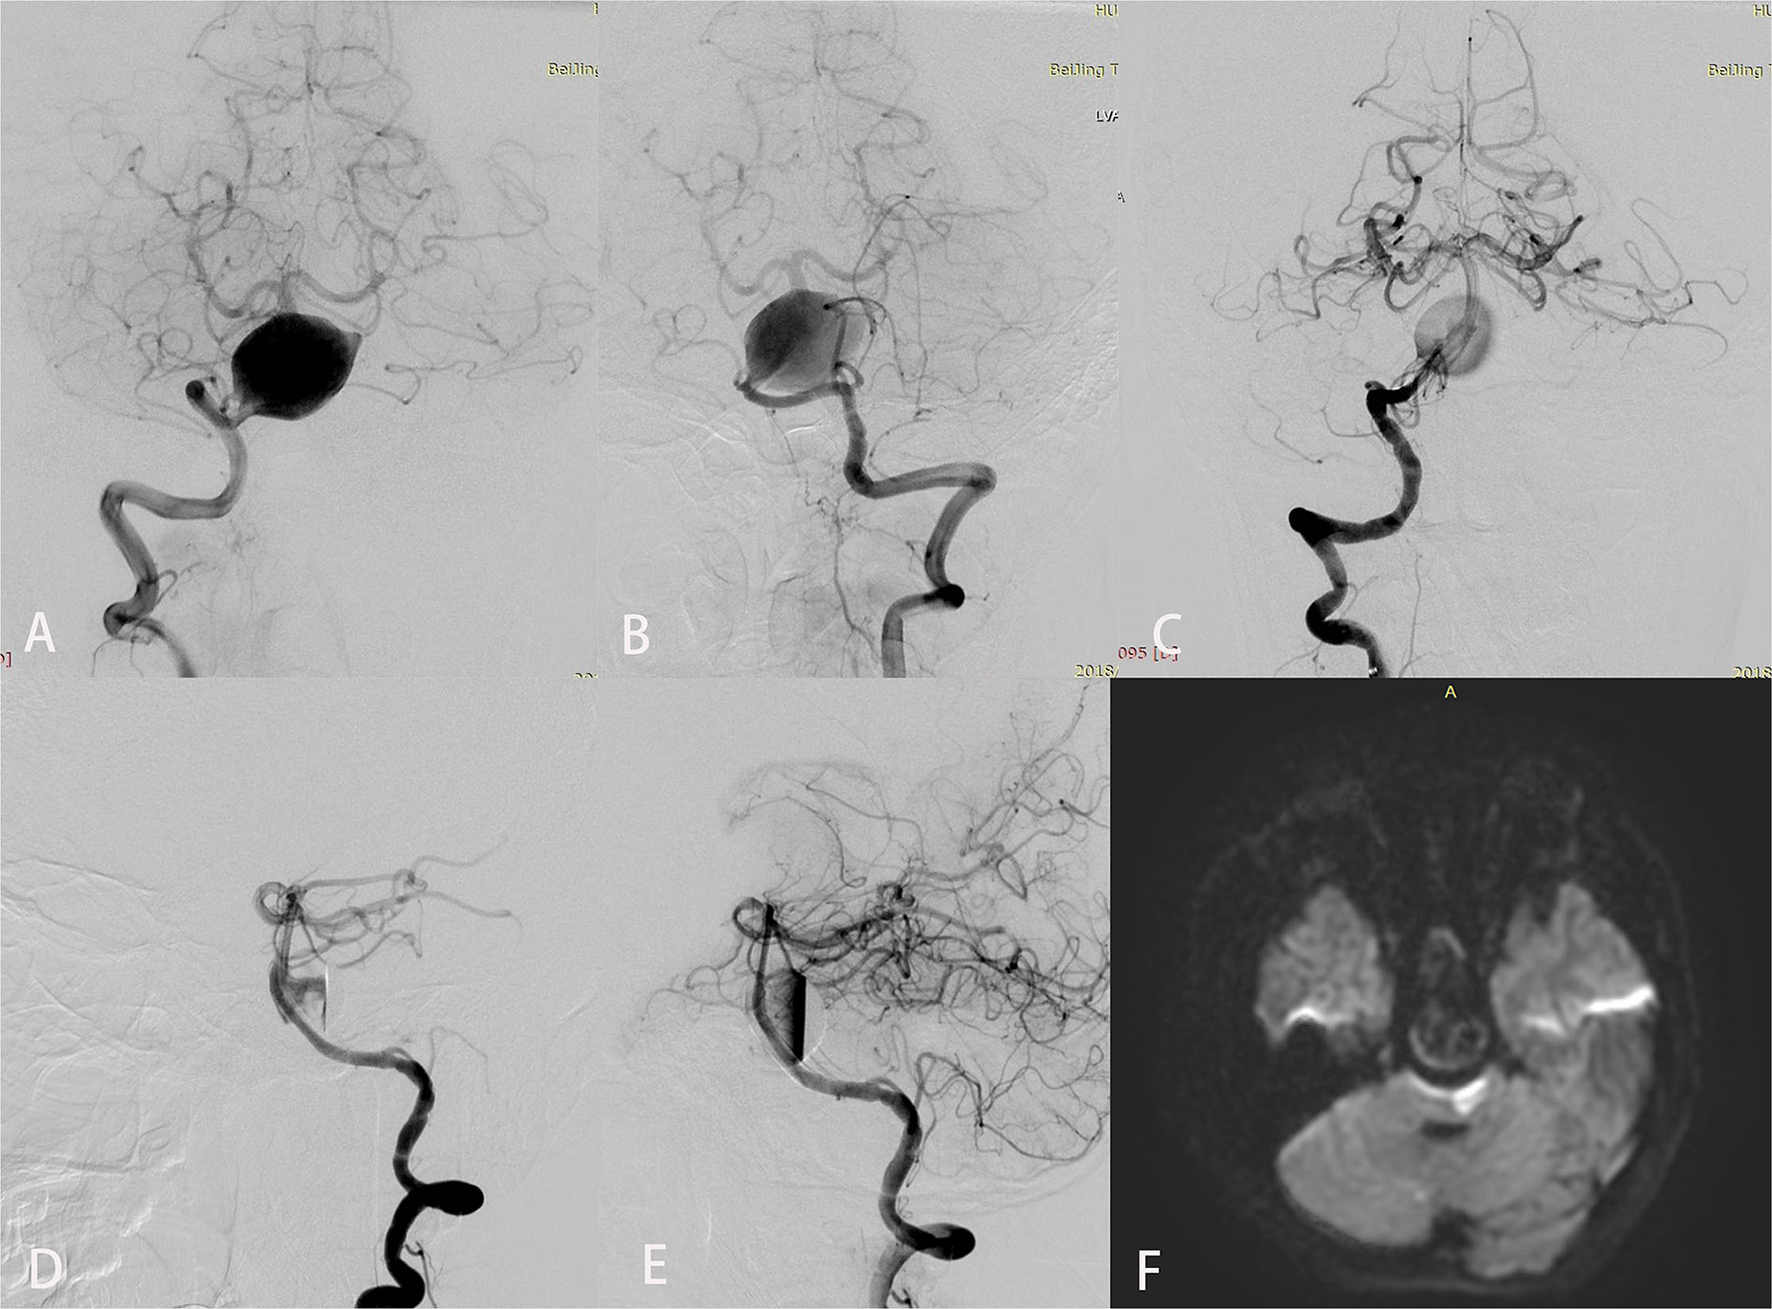

Periprocedural complications included ischemic stroke in five patients, worsening mass effect in three, and delayed cerebral hemorrhage in four. Among the ischemic strokes, four were perforator strokes and one was embolic; all five were treated with telescopic PEDs (mean number of PEDs used, 2.4 [range, 2–4]). Case 7 experienced acute onset dysarthria and right hemiplegia 12 h after placement of four PEDs. CT and MRI showed a large brainstem infarct with no hemorrhage. After a 24-h tirofiban infusion, the patient's symptoms gradually resolved. However, on postprocedure day 3, headache and vomiting developed, which rapidly progressed to loss of consciousness, cardiorespiratory arrest, and death before CT could be performed. Relevant imaging studies are shown in Figure 1. Delayed aneurysmal rupture was the presumed cause of death. Other patients who developed neurological symptoms after the procedure also underwent CT to exclude hemorrhage and infusion of tirofiban for 24 h: cases 11 and 18 recovered completely but cases 8 and 21 had mild residual single-limb paresis (final mRS score 2).

Figure 1

Imaging studies for a 12-year-old boy (case 7) who presented with an 8-month history of chronic headaches and vertigo. Preoperative anteroposterior views of right (A) and left (B) vertebral angiography showed a giant fusiform basilar artery aneurysm. Anteroposterior (C) and lateral (D) views of right vertebral angiography immediately after treatment demonstrated excellent reconstruction of the basilar artery with 4 Pipeline embolization devices. An inflow jet is seen in the early arterial phase in (D). (E) In the late arterial phase, contrast stasis is seen in the lumen of the aneurysm. Diffusion-weighted imaging (F) obtained to evaluate dysarthria and right hemiplegia that developed 12 h after the procedure showed a large brainstem infarct.